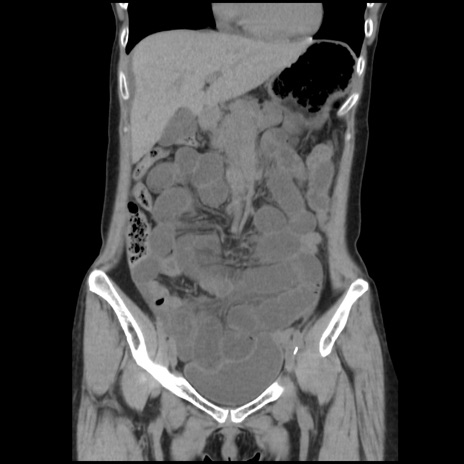

症例32(冠状断像)

【症例】40歳代 女性

【主訴】上腹部痛、嘔気・嘔吐

【現病歴】約9時間前頃から急に上腹部痛、嘔気、嘔吐が出現。改善しないため救急要請。

【既往歴】子宮頚癌(広汎子宮全摘術、放射線療法)、腸閉塞

【身体所見】腹部:平坦、軟、腸雑音亢進、上腹部を中心に腹部全体に圧痛あり。

【データ】WBC 8400、CRP 0.03